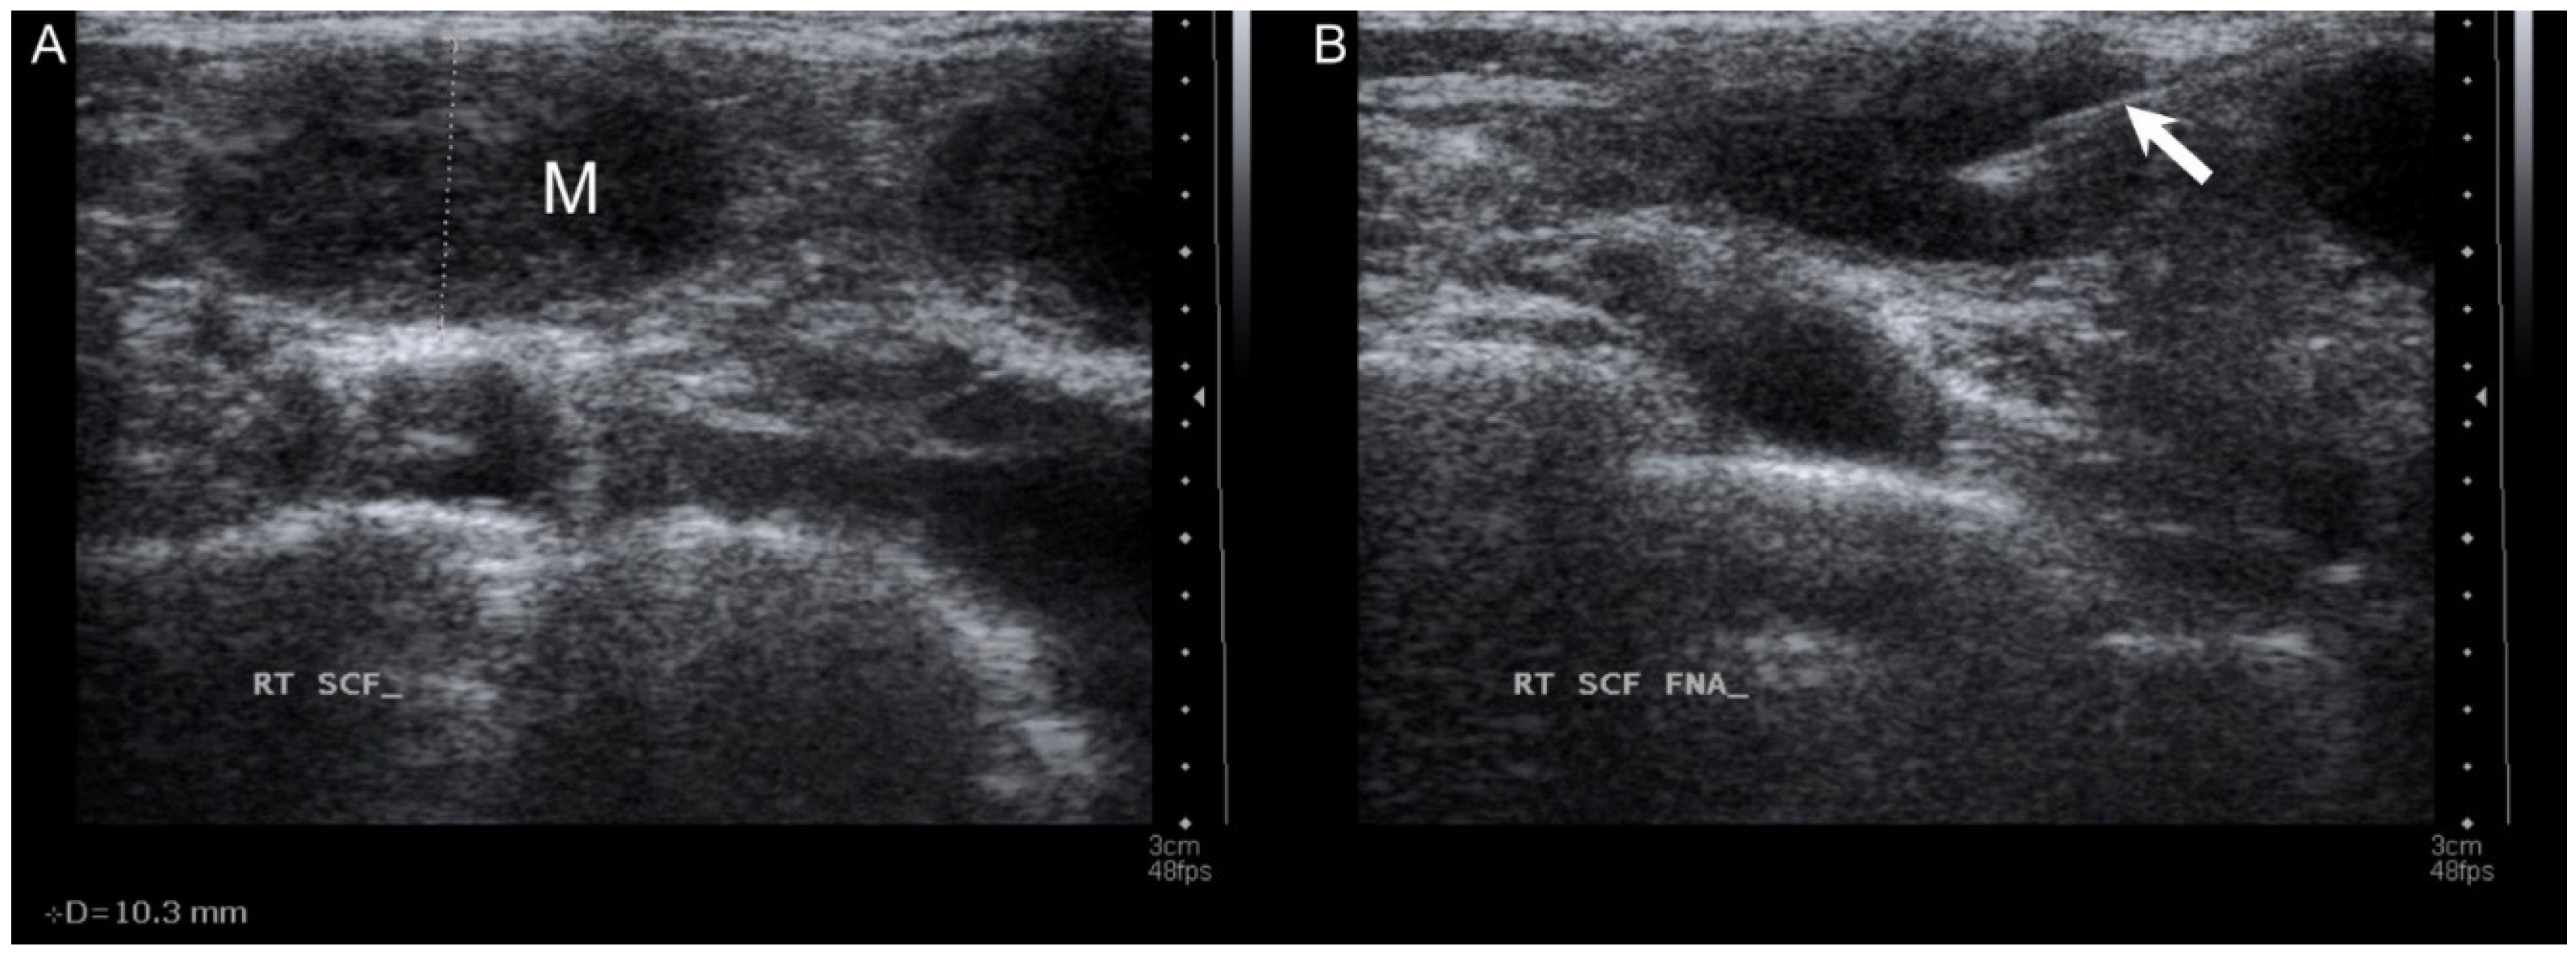

2. Case Report